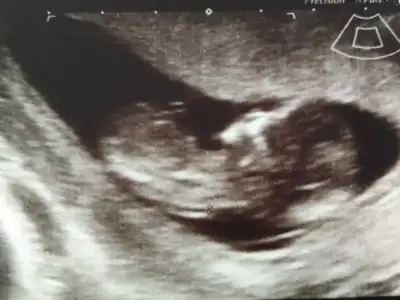

bu daha iyi oldu sanırım :) :nazar::anneadayı: